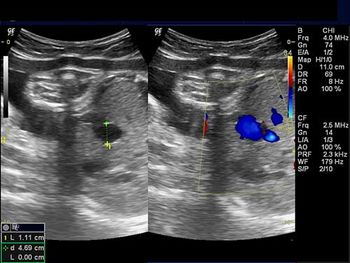

Challenge your diagnostic skills: Is everything normal in this fetal abdomen?

Challenge your diagnostic skills: What's the diagnosis and prognosis based on these images of the fetal brain in a third trimester pregnancy?

Challenge your diagnostic skills: Is everything fine with this third trimester pregnancy?